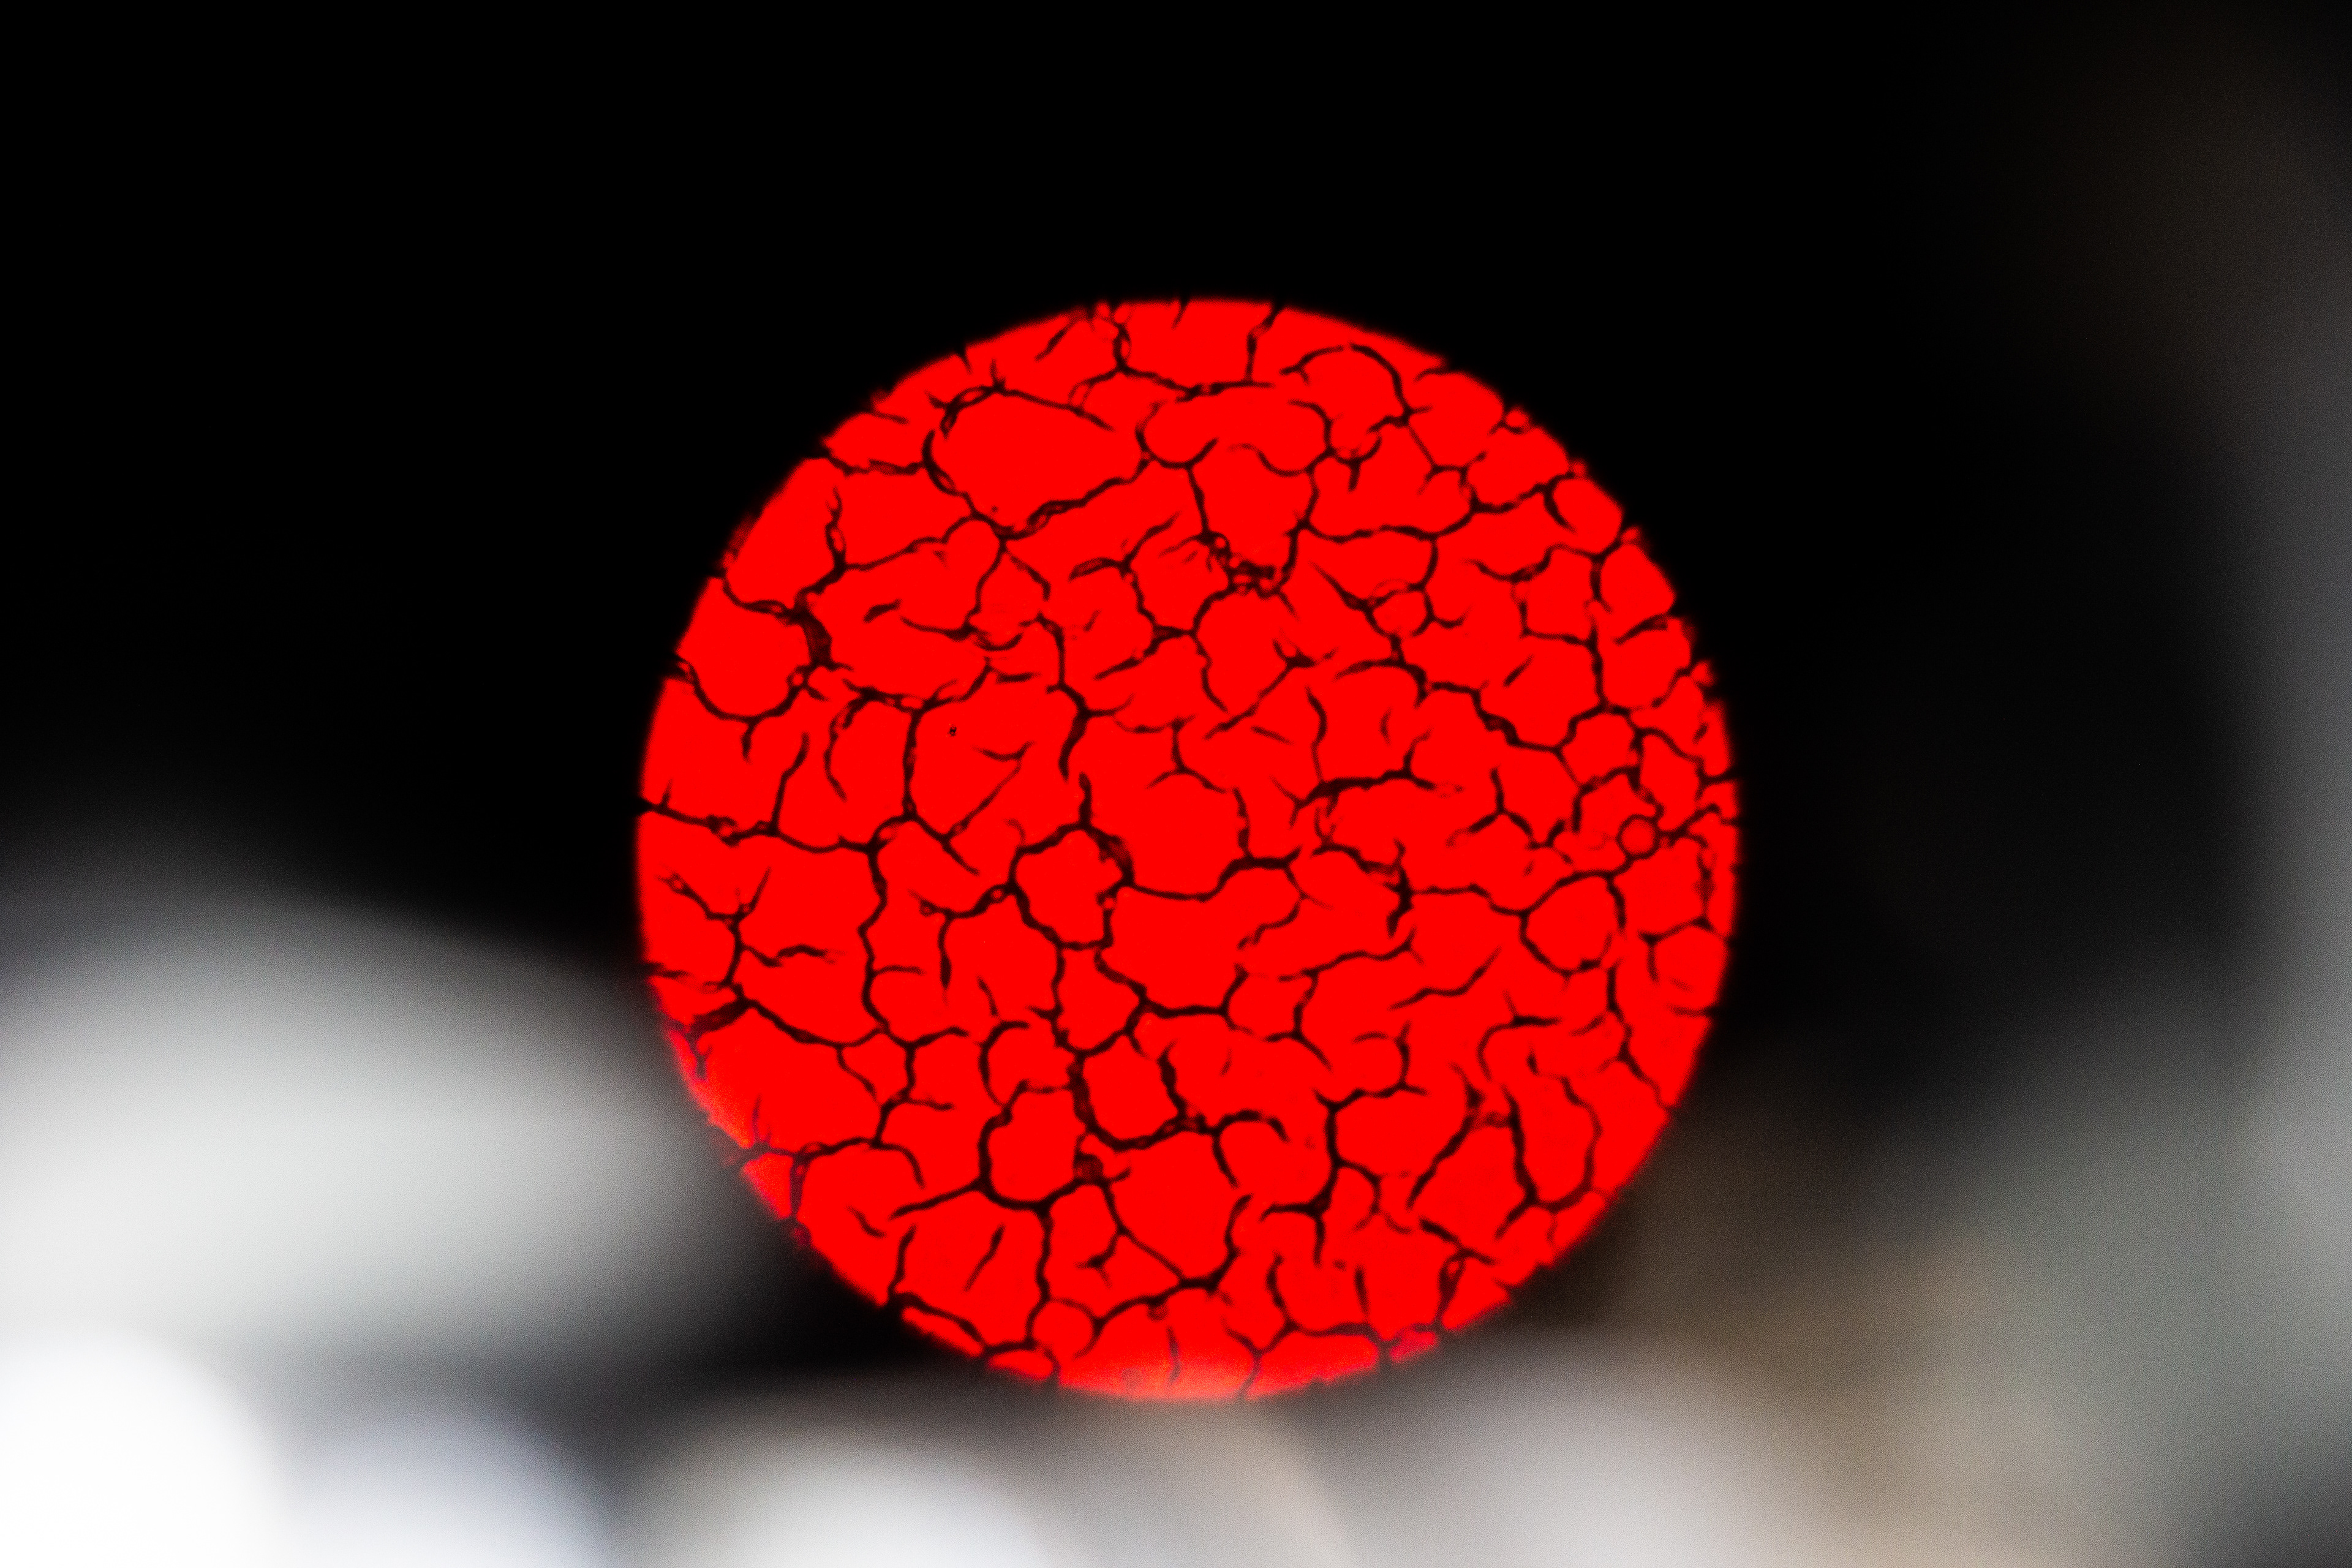

This got me curious. So, I collected and analyzed my own menstrual blood. First I took a look at my venous blood from my small finger and then compared it to my menstrual blood. The following pictures show my menstrual blood at different magnifications:

Menstrual Blood 40x